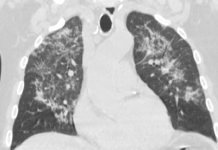

La TC toracica senza MdC ha documentato la presenza di opacità ground glass (GGO) a distribuzione subpleurica e peribroncovascolare del lobo superiore sinistro (LSS) e della lingula (Fig. 1, 2, 3); il lobo inferiore sinistro (LIS) e il polmone destro erano normali. L’ipotesi diagnostica radiologica, formulata sulla base dell’ imaging, è stata di polmonite virale (infezione da SARS-CoV-2), confermata dalla reazione a catena della polimerasi della trascrizione inversa in tempo reale (RT-PCR) [1, 2].

Dopo 40 giorni il paziente è stato sottoposto a follow up mediante indagine TC del torace senza MdC che ha documentato parziale regressione delle note alterazioni GGO precedentemente segnalate al LSS e lingula (Fig. 4, 5, 6).

La polmonite da COVID-19 tende a manifestarsi all’indagine TC toracica sotto forma di opacità GGO subpleuriche bilaterali con broncogramma aereo, margini mal definiti e una leggera predominanza nel lobo inferiore destro [3-5]. Questi pattern TC polmonari sono altamente aspecifici e potrebbero sovrapporsi ai segni radiologici dell’influenza H1N1, polmonite da citomegalovirus, altri coronavirus (SARS, MERS) o polmonite atipica [6-8]. Pan et al [9] hanno studiato 21 pazienti con COVID-19 a intervalli di circa 4 giorni dall’inizio della malattia fino al recupero clinico mediante indagini TC toraciche. Hanno definito 4 fasi del coinvolgimento polmonare alla TC e hanno documentato che le alterazioni polmonari alla TC toracica mostrano la massima gravità circa 10 giorni dopo l’insorgenza dei sintomi. Questo caso clinico illustra un coinvolgimento polmonare unilaterale e unilobare in un paziente con infezione da SARS-CoV-2, confermata al tampone, e con sintomi respiratori da 8 giorni. Sebbene la presenza di lesioni unilaterali nella polmonite COVID-19 suggerisce che la malattia è nella sua fase iniziale, ipotizziamo che questi reperti TC di coinvolgimento unilaterale e unilobare possano essere presenti anche in fase clinica progressiva.